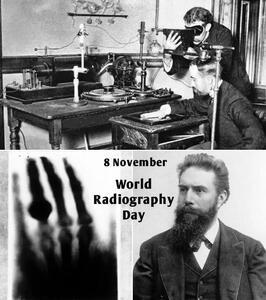

اشعه ایکس

اسکن اشعه ایکس به معمای چگونگی قرار گرفتن تابوت بدون دریچه لیدی چنت پاسخ میدهد.

سامسونگ به دلیل عدم رعایت استانداردها و قرار گرفتن ۲ کارمند در معرض اشعه ایکس کمتر از ۸ هزار دلار جریمه شد.

شرکت سامسونگ به دلیل عدم رعایت استانداردها ۸ هزار دلار جریمه شد.

کشف بزرگترین الماس قرن با اشعه ایکس! - تکناک

شرکت کانادایی Lucara Diamond با استفاده از فناوری انتقال اشعه ایکس، دومین الماس بزرگ جهان را در بوتسوانا کشف کرده است.

اشعه ایکس با دوز پایین میتواند سلولهای تومور مغزی را نابود کند!

پروفسور Pu Kanyi نویسنده ارشد و همکار این مطالعه گفت: «ما از دوزهای بسیار پایین اشعه ایکس و MRAPهای کشنده سرطان استفاده کردیم.